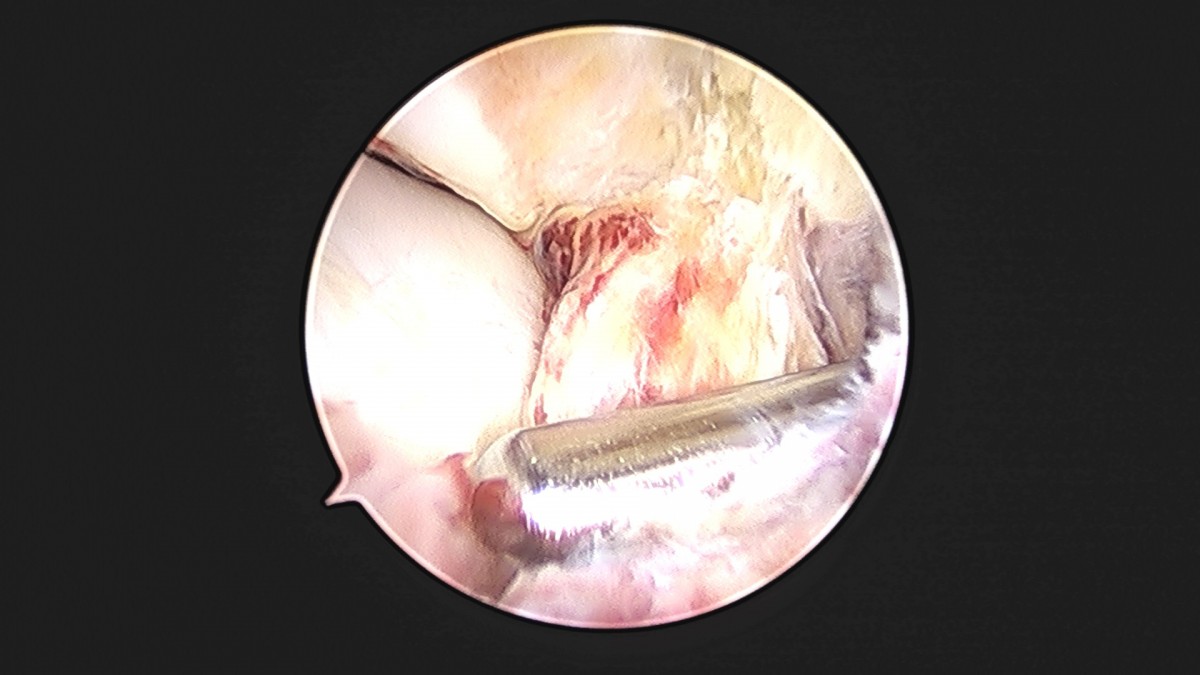

이재상원장님 발목 인대 봉합술 박찬O 환자

dae765e4d9ac96aee867c9d6292d8784_1758007286_1952.jpg